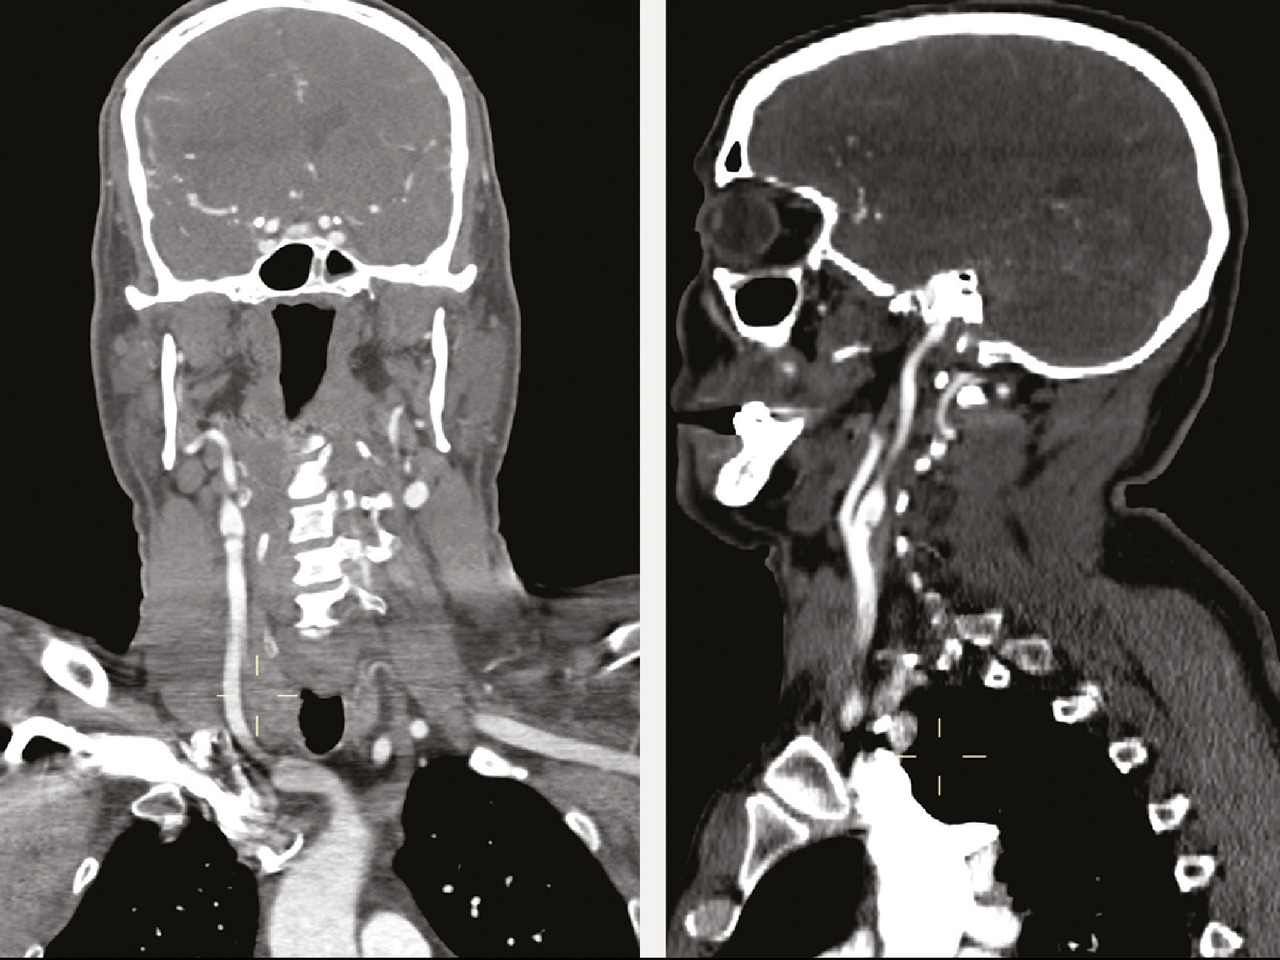

Cet homme de 41 ans, sans antécédent notable, était admis aux urgences pour une hémiplégie gauche d’apparition brutale (H3). Une angio-IRM cérébrale montrait un infarctus frontal et dans le territoire de l’artère sylvienne superficielle et profonde droit (fig. 1 ). Étant donné son jeune âge, un angioscanner des troncs supra-aortiques était réalisé, montrant une image d’éperon caractéristique de diaphragme bulbaire carotidien (fig. 2 ). Le patient était hospitalisé, mis sous traitement médical à base d’anticoagulant à dose préventive et d’antiagrégant plaquettaire en attendant la réalisation d’une artériographie avec mise en place d’un stent.

Le diaphragme carotidien est une pathologie rare à l’origine d’accidents vasculaires cérébraux ischémiques du sujet jeune. Il s’agit d’une prolifération intimale située le plus souvent à la face postérieure du bulbe carotidien réalisant un voile endoluminal, entraînant la formation d’emboles et responsable d’infarctus cérébraux par embolie des grosses artères ; son diagnostic est essentiel parce qu’il expose à un risque élevé de récidive dans le même territoire vasculaire. L’angioscanner des troncs supra-aortiques avec reconstruction en coupe sagittale montre un éperon endoluminal caractéristique. Le siège de prédilection est le bulbe carotidien ; d’autres localisations ont été décrites, notamment la carotide commune1 et l’artère carotide interne. L’angiographie numérisée à but thérapeutique montre le diaphragme, la stase du flux sanguin dans le récessus créé et, image caractéristique, la stagnation du produit de contraste. Le traitement consiste en un stenting endovasculaire et une endartériectomie associée à une antiagrégation plaquettaire à vie ;2 une surveillance rapprochée est préconisée, nécessitant un examen neurologique et une échographie doppler 3 mois après, puis annuellement pendant 5 ans. La double antiagrégation plaquettaire est préconisée pendant 3 mois, donnant relais à une monothérapie à base d’aspirine à vie.